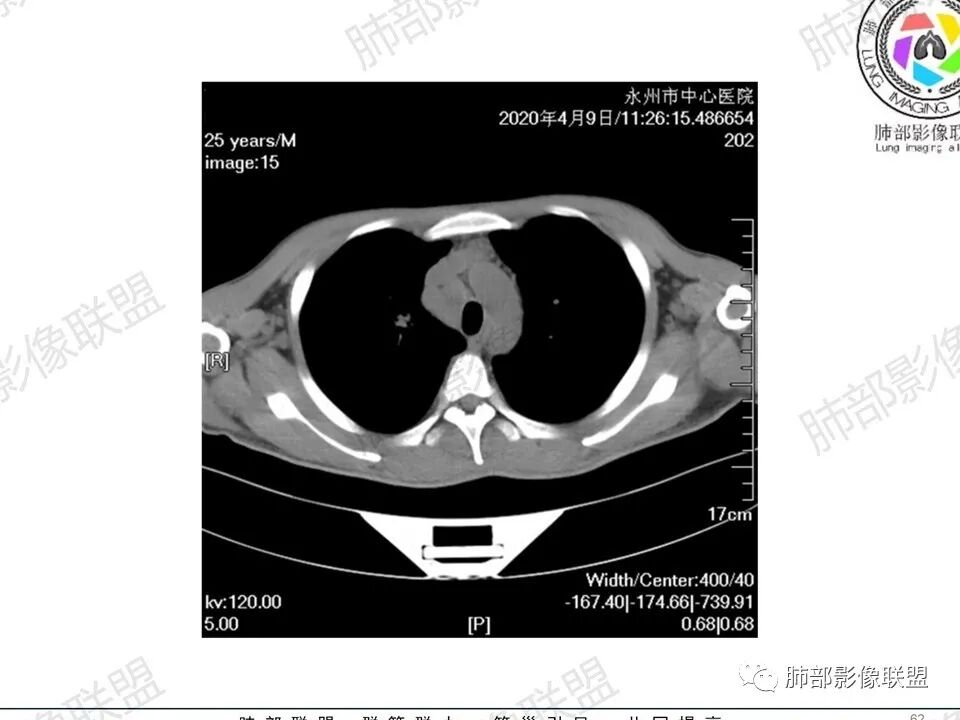

3、影像表现:双肺散在斑片影及结节影,部分结节内可见血管穿行,斑片影沿支气管血管束分布,近胸膜侧病变收缩不明显。部分中央淋巴间质增厚,小叶间隔增厚。病灶内支气管穿行,部分支气管略扩张。局部小结节呈串珠样改变。纵隔、肺门区、锁骨上及腋窝淋淋巴结肿大,部分有融合。心腔低密度。脾大。

5.双肺门及纵隔淋巴结显著增大,这改变相当显眼。这里强调“双肺门”及“多发”!

增大的淋巴结密度偏低且均匀。此外患者有体表淋巴结增大。

6.心腔密度减低。提示可能存在贫血。

1.临床表现明显,纵隔及双肺门淋巴结显著肿大,临床最为担心的还是淋巴瘤!

淋巴瘤肺部浸润表现多样,多发结节影是其最常出现的影像学改变,尤其是霍奇金病。